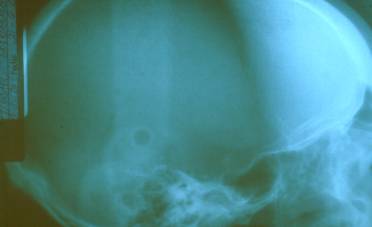

La radiografía de cráneo se encuentra dentro de límites normales. Fig. 4

Figura 4 Rx de Cráneo